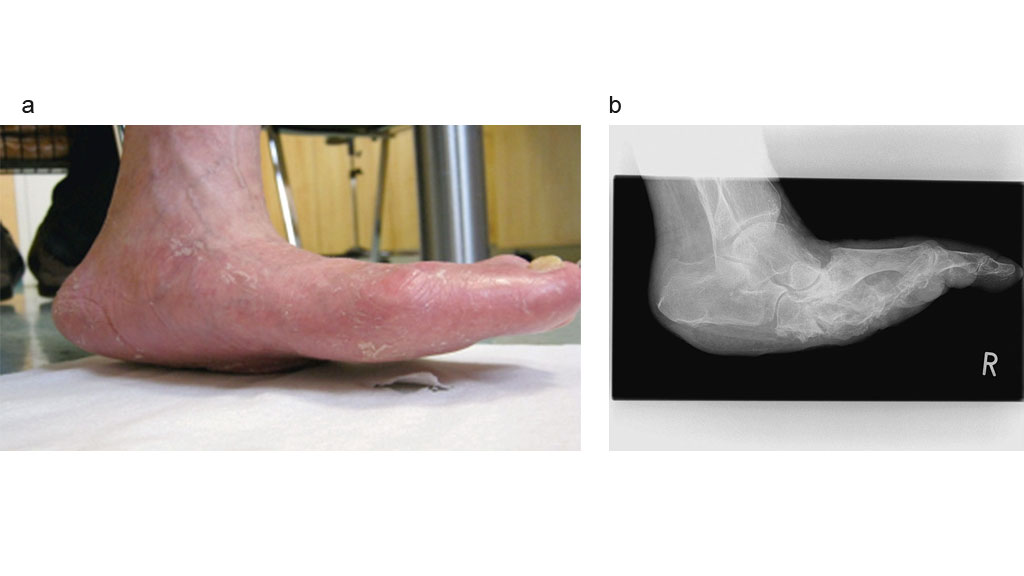

Klassifikation der Wundsituation nach Wagner/Armstrong

Während bei der gesunden Fußstellung durch Druckumverteilung die Belastung im Bereich der Zehenspitzen und im Bereich der Mittelfußköpfchen bei intaktem Quer- und Längsgewölbe auf die gesamte Fußsohle übertragen wird, erfolgt beim diabetischen Fuß durch Gefäß‑, Sehnen- und Knochenveränderungen eine Veränderung der normalen Fußstellung. Dabei wird vorrangig über einen neurogenen Hohlfuß und weitere Mittelfußveränderungen die punktuelle Belastung dramatisch beeinflusst. Im Ergebnis bricht das Fußgewölbe innerhalb einer zeitlichen Komponente allmählich komplett in sich zusammen und aus dem neurogenen Hohlfuß entsteht ein deformierter und instabiler Stempelfuß (Abb. 4a u. b).

Dieser „Risikofuß“ lässt sich durch konservative Maßnahmen wie medizinische Fußpflege, durch konsequentes Abtragen der Hornhaut (Podologie) und durch Entlastung in Form von geeignetem Schuhwerk (spezialisiertes Schuhhandwerk) dahingehend beeinflussen, dass die Schädigungen des Fußes stationär bleiben.